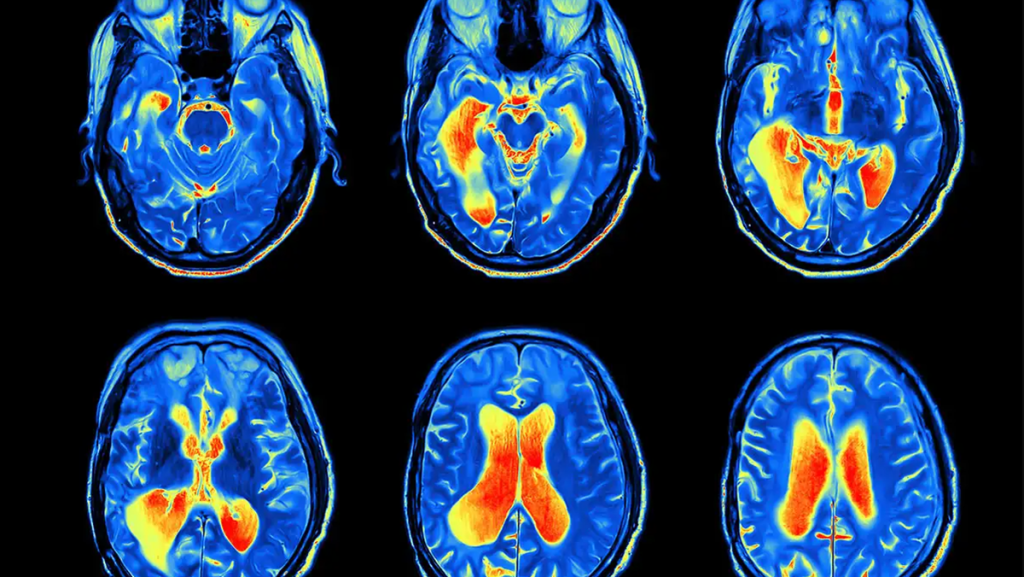

Sipas ekspertëve nga Universiteti i Tsukuba, në Japoni, disa minuta vrap ju lejojnë të rrisni rrjedhjen e gjakut në zonat e korteksit dypalësh paraballor, pjesa e trurit që luan një rol të rëndësishëm në kontrollin e humorit dhe funksionet ekzekutive.

“Për të kryer lëvizjen shtytëse të vrapimit, nevojiten funksione koordinimi dhe ekuilibri, të cilat përcaktojnë aktivizimin neuronal të korteksit paraballor dhe pritet që funksionet e tjera që i referohen këtij rajoni të trurit të mund të përfitojnë nga rritja e burimeve të trurit”, shpjegon biokimisti Hideaki Soya, autor kryesor i studimit.

“Ne tashmë e dimë, nga kërkime të tjera se aktiviteti fizik në përgjithësi përmirëson shëndetin fizik dhe mendor, por janë bërë relativisht pak analiza mbi përfitimet konkrete të vrapimit në krahasim me sportet e tjera, si çiklizmi”, shtoi ai.